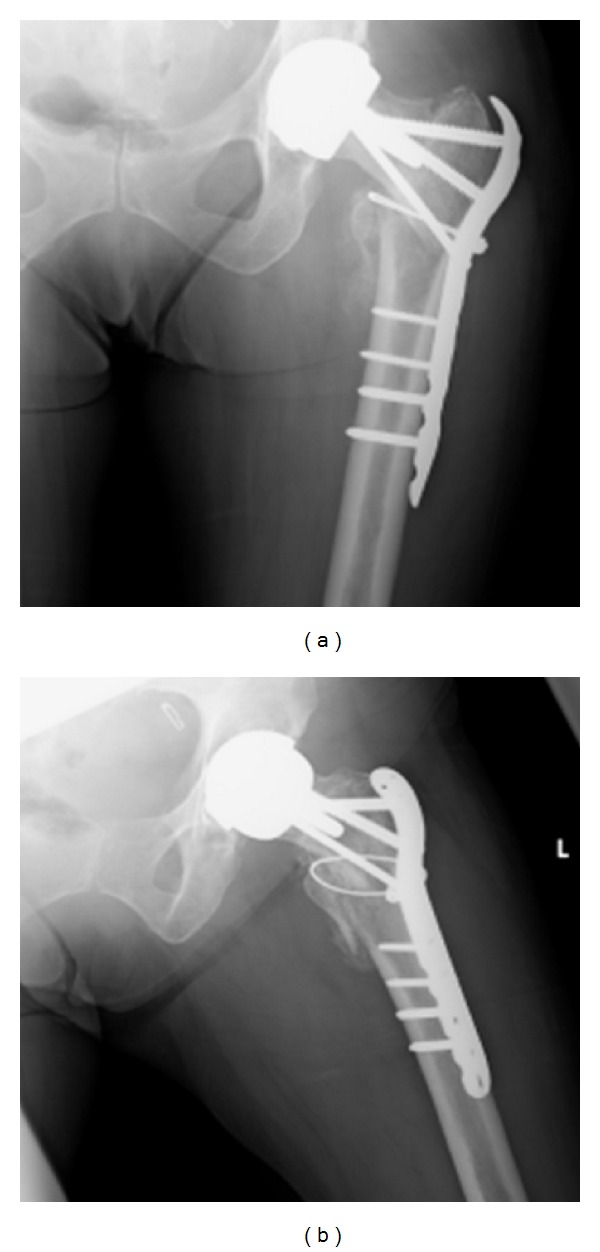

Mrs. X was reviewed six weeks post-operatively and it was noted that her fracture had collapsed slightly and the hip had slipped into a more varus position (see Figure 5). At this stage light partial weight bearing was continued and a review was arranged for a further six weeks.

Figure 5.

(a)-(b) Images taken at 6-week postoperation review.